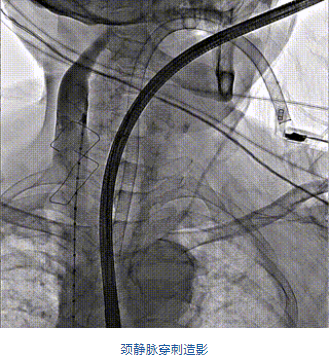

2022年5月27日,四川大學(xué)華西醫(yī)院心臟內(nèi)科陳茂、馮沅教授帶領(lǐng)的瓣膜病介入治療多學(xué)科團(tuán)隊(duì),在國(guó)內(nèi)首次采用純介入方式通過穿刺右側(cè)頸靜脈成功完成經(jīng)導(dǎo)管三尖瓣置換。植入的人工瓣膜是具有中國(guó)自主知識(shí)產(chǎn)權(quán)的LuX-Valve Plus系統(tǒng)。術(shù)中上海長(zhǎng)海醫(yī)院陸方林教授和喬帆副教授給予了在線支持。

團(tuán)隊(duì)前期經(jīng)過多次討論,制定了周密的手術(shù)策略和預(yù)案。由于患者已是近九旬的超高齡老人,傳統(tǒng)外科開胸手術(shù)風(fēng)險(xiǎn)極高,純介入經(jīng)血管三尖瓣替換能夠明顯減少創(chuàng)傷。術(shù)中陳茂及馮沅教授結(jié)合體表定位在造影指示下精準(zhǔn)穿刺右側(cè)頸靜脈并預(yù)置兩把血管縫合器。成功建立經(jīng)皮血管入路后在食道超聲和DSA的引導(dǎo)下順利完成人工瓣膜植入,術(shù)后超聲和造影顯示人工三尖瓣同軸性良好,瓣架固定牢靠,無反流和瓣周漏,平均跨瓣壓差降為1mmHg。術(shù)畢收緊預(yù)置的血管縫合器縫線完成止血,縫合效果滿意,在手術(shù)室即刻拔除氣管插管。